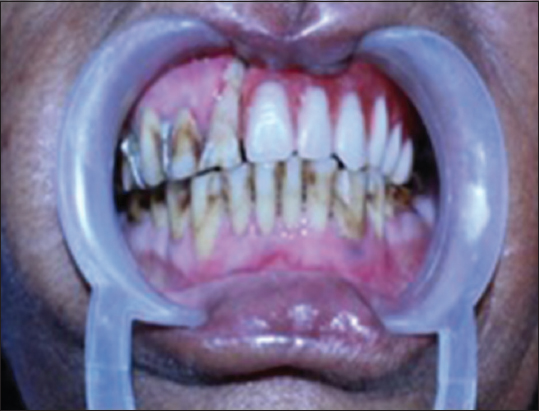

A patient aged 68 years reported to the department of prosthodontics with mucoepidermoid carcinoma of the left side of the palate [Figure 1]. The chief complaint of the patient was the inability in chewing and swallowing the food. On intraoral examination, there was a swelling seen on the left side of the palate which was 2 cm × 2 cm in dimension. The maintenance of oral hygiene was very poor.

thumb

Figure 1: Intraoral view showing mucoepidermoid carcinoma